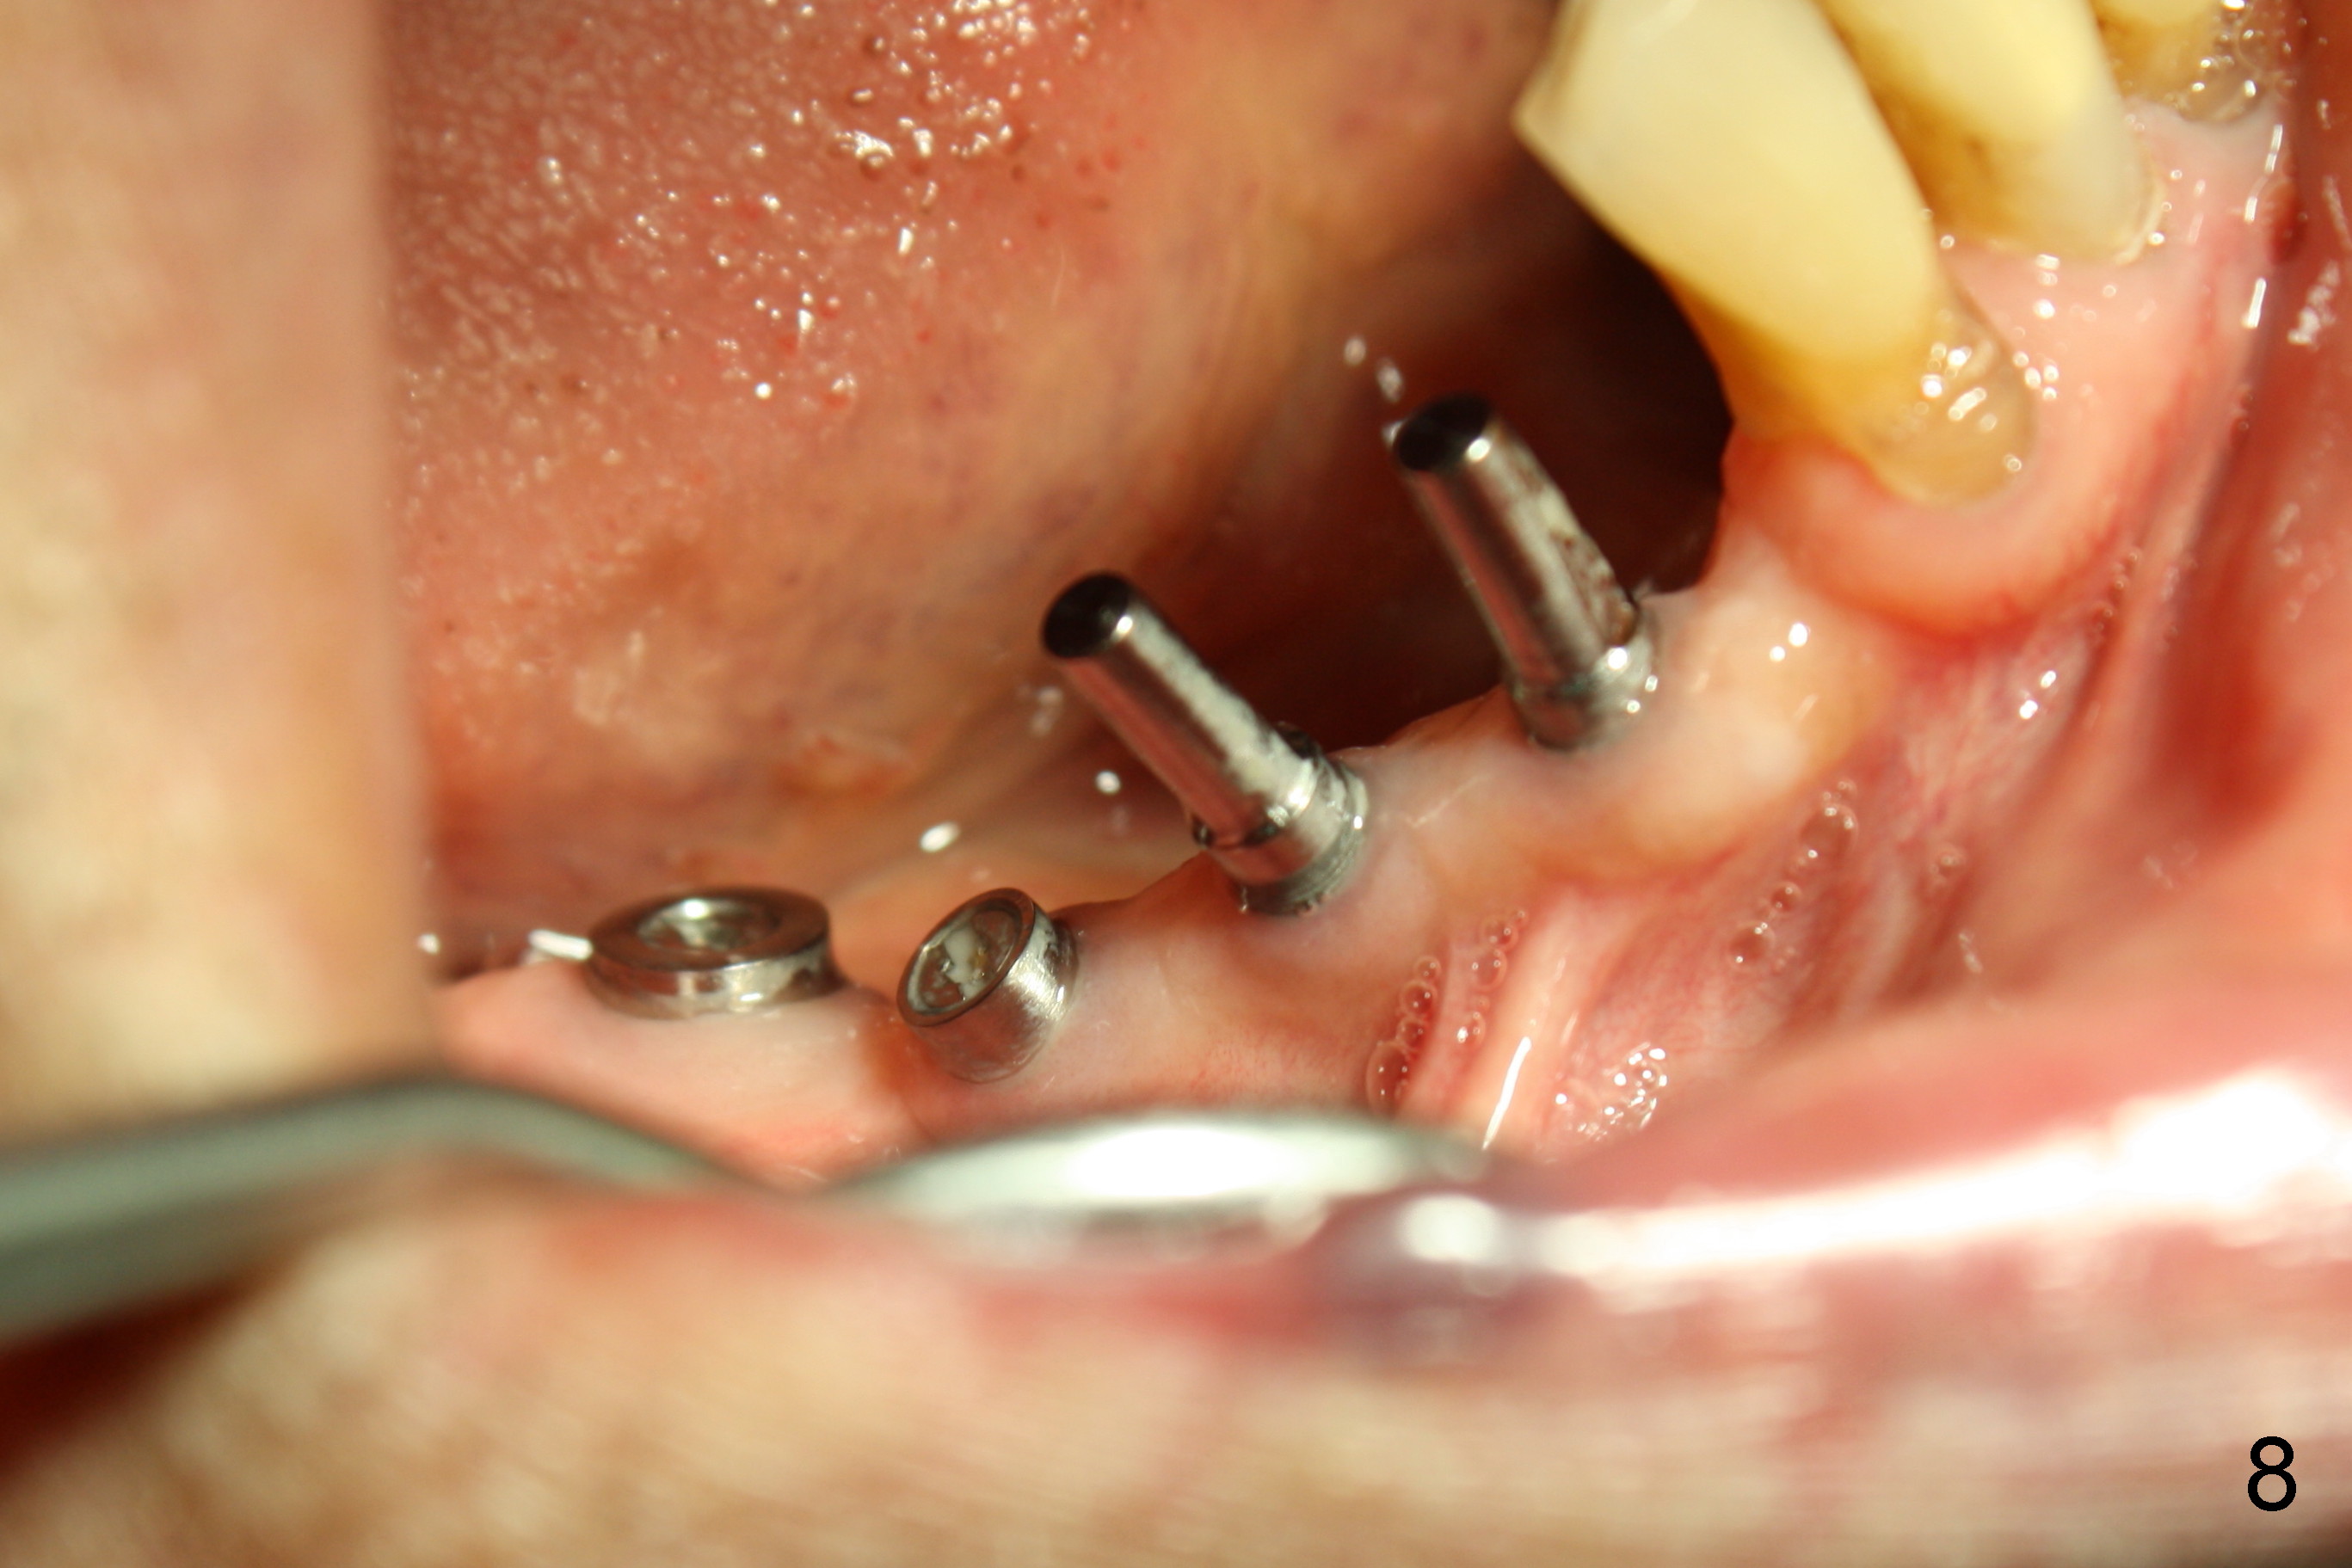

The lower right bridge (from canine (Fig.2: 3) to 1st molar (Fig.1: 6)) fails while a 77-year-old man is undergoing chemotherapy for urinary bladder cancer.  The abutments of the bridge are extracted without plan for implants (Fig.4).   Four months later, the patient returns for implants (Fig.3), but the ridge is narrow (Fig.5).  While 2 of 3x14 mm 1-piece implant are placed at the canine and 1st bicuspid sites, 2 piece ones at the 2nd bicuspid and 1st molar sites (Fig.6: 3.5x11 mm, 5x14 mm).  Soft (Fig.7-10) and hard (Fig.11) tissues heal 1 week (Fig.7) and 4 months (Fig.8-11).  There is minimal bone resorption 1 year 7 months post cementation (Fig.12,13, non-splinting).  It appears that narrow diameter implants are a valid solution to narrow ridge at the sites of the lower canine and premolar.  As long as there are enough implants for function, the crowns are not necessary to be splinted.  Surprisingly, the patient starts flossing after implant restoration.  Retrospectively an immediate provisional bridge should have been fabricated.